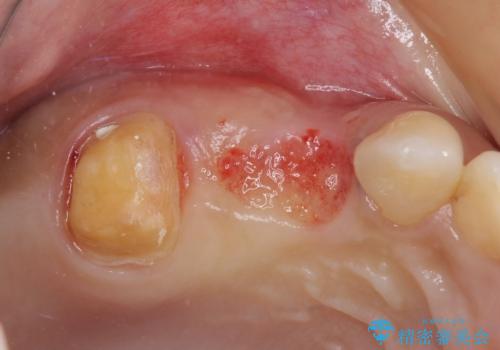

- 冷たいものがしみたり、ものが挟まったり、噛んだときに痛んだりするとのことで来院された患者様です。

レントゲン写真などで診査した結果、奥歯の銀歯の下にはむし歯が多く存在し、右上の奥歯は歯根が破折していました。

破折した歯を抜去し、インプラントによる補綴を行うこととしました。